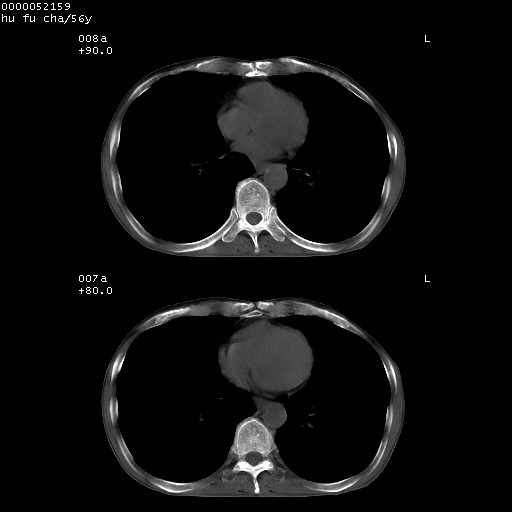

以下是引用zsl6918在2008-8-25 22:47:00的发言:[br]胸骨,胸椎及肋骨均可见多发转移表现,肝内低密度结节不除外转移。原发灶可能在右肺。双侧可见支扩表现。

以下是引用宇宙ct在2008-8-25 23:26:00的发言:[br][br] 胸骨,胸椎及肋骨均可见多发转移表现,肝内低密度结节不除外转移。原发灶可能在右肺。双侧可见支扩表现。 [br] [br]

以下是引用卜一在2008-8-26 8:02:00的发言:[br][br] 支持:肺癌并肺内,胸骨,胁骨,胸椎及肝内转移!另:左肺支气管扩张征伴感染! [br]

以下是引用zjzjr在2008-8-26 11:03:00的发言:[br]支持:肺癌并肺内,胸骨,胁骨,胸椎及肝内转移!另:左肺支气管扩张征伴感染!